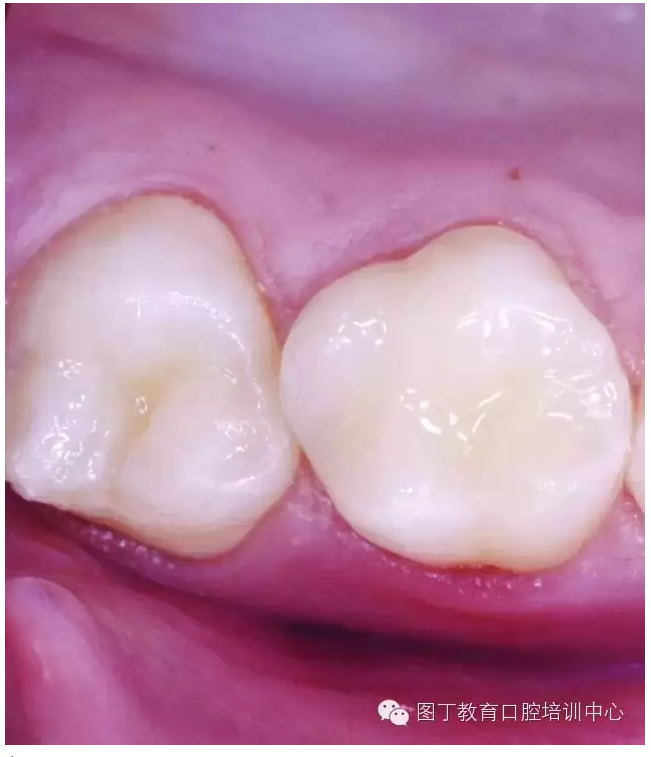

窩溝封閉后

高質(zhì)量的封閉,對于任何年齡的都有益